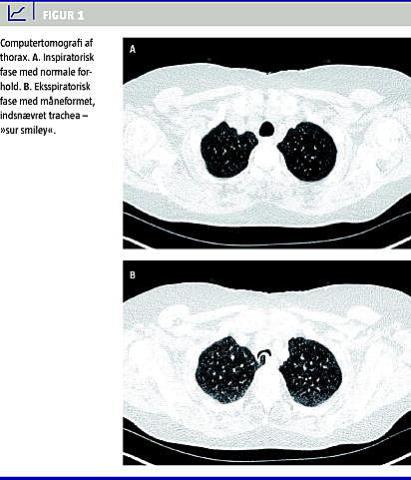

En 70-årig kvinde blev henvist fra en speciallæge i lungemedicin til højresolutionscomputertomografi (HRCT) af thorax på mistanke om pulmonal årsag til tre års kraftig hoste. Periodevist var denne hoste socialt invaliderende, og patienten havde været igennem en længere udredning og forskellige behandlingstiltag uden effekt. Der var taget røntgen af thorax, røntgen af øsofagus, udført laryngoskopi, forsøgt protonpumpehæmmer mod reflukssymptomer og givet beta-2-agonist på mistanke om astma. Den primære mistanke var på dette tidspunkt bronkieektasier eller interstitiel lungesygdom. Der blev foretaget HRCT i såvel inspiratorisk som eksspiratorisk fase, og undersøgelsen viste normale forhold i lungeparenkymet i begge faser samt normale forhold i trachea i inspirationsfasen (Figur 1 A). Men i eksspiratorisk fase så man tydeligt, hvorledes trachea komprimeredes markant, således at lumen fremstod indsnævret og halvmåneformet i hele tracheas forløb og faktisk tillige i hovedbronchi (Figur 1B), således at der var tale om trakeobronkomalaci. Man kan billeddiagnostisk mnemoteknisk karakterisere dette mønster som en »sur smiley", og det er helt foreneligt med diagnosen TM. Desuden sås der hos denne patient et atypisk forløb af øsofagus, som fik en pseudoudposning i eksspiratorisk fase. I inspiratorisk fase kunne ingen af disse anomalier ses, og således er eksspirationsfasen helt essentiel for diagnostikken.